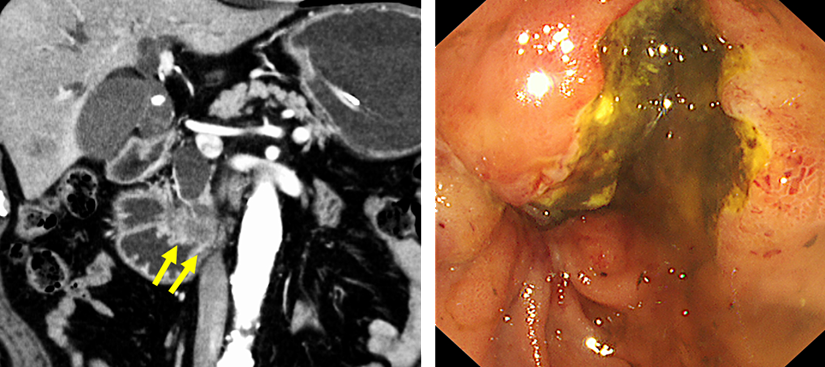

術後の胆管空腸吻合部の再発に対する胆道ドレナージ

肝門部領域胆管癌の術後に胆管空腸吻合部に再発を認めた症例です。

本症例はRoux-en-Y再建後であり、ダブルバルーン内視鏡を用いて胆管まで到達しました。胆管造影を行い、狭窄部を確認した後、前区域枝に2本、後区域枝に1本、合計3本のステントを留置しました。

左上:Roux-en-Y再建後でした。ダブルバルーン内視鏡を用いました。

右上:到達後、胆管造影を行い、狭窄部の確認をしました。

左下・右下:前区域枝に2本・後区域枝に1本のステントを留置しました。